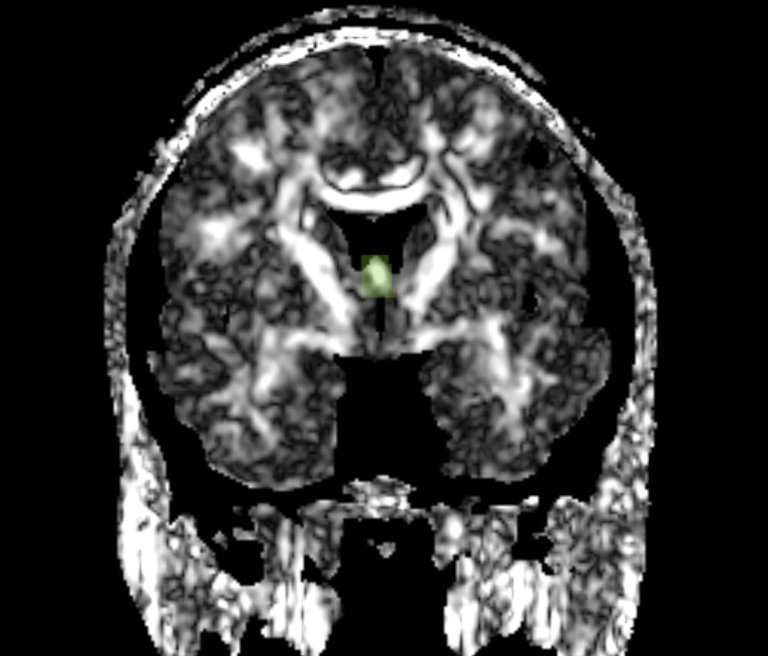

We apply fiber tractography to quantify fornix Fractional Anisotropy (FA) in schizophrenia. Two ROI method (shown in the figures) were used to extract left and right fornix in 34 chronic schizophrenia subjects and 40 matched controls, and mean FA along the entire tract was extracted separately for the left and the right sides and compared between groups. Preliminary data indicate bilateral decreased FA in the fornix of schizophrenics.